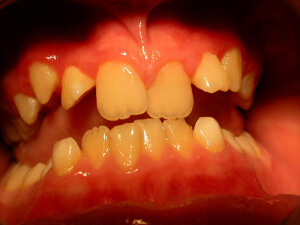

Gingivitis

Gingivitis is caused to the bacterial dental plaque. The main problems related to gingivitis are bleeding from the gums (during tooth brushing), halitosis and swelling of the gums.

Except for the bad oral hygiene, gingivitis is related to hormonal changes during puberty or pregnancy, or the presence of orthodontic mechanisms in the mouth that make difficult to maintain good oral hygiene.